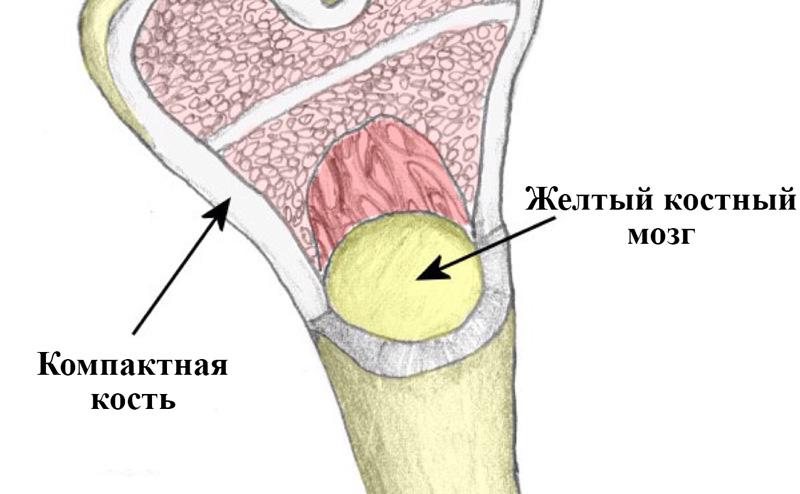

Изучение костного мозга: анатомия и функции